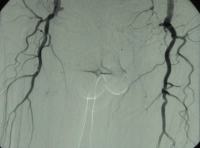

DSA preoperatoria del paciente:

PM 311-7

Abb. 7: Fußbögen stellen sich nicht dar